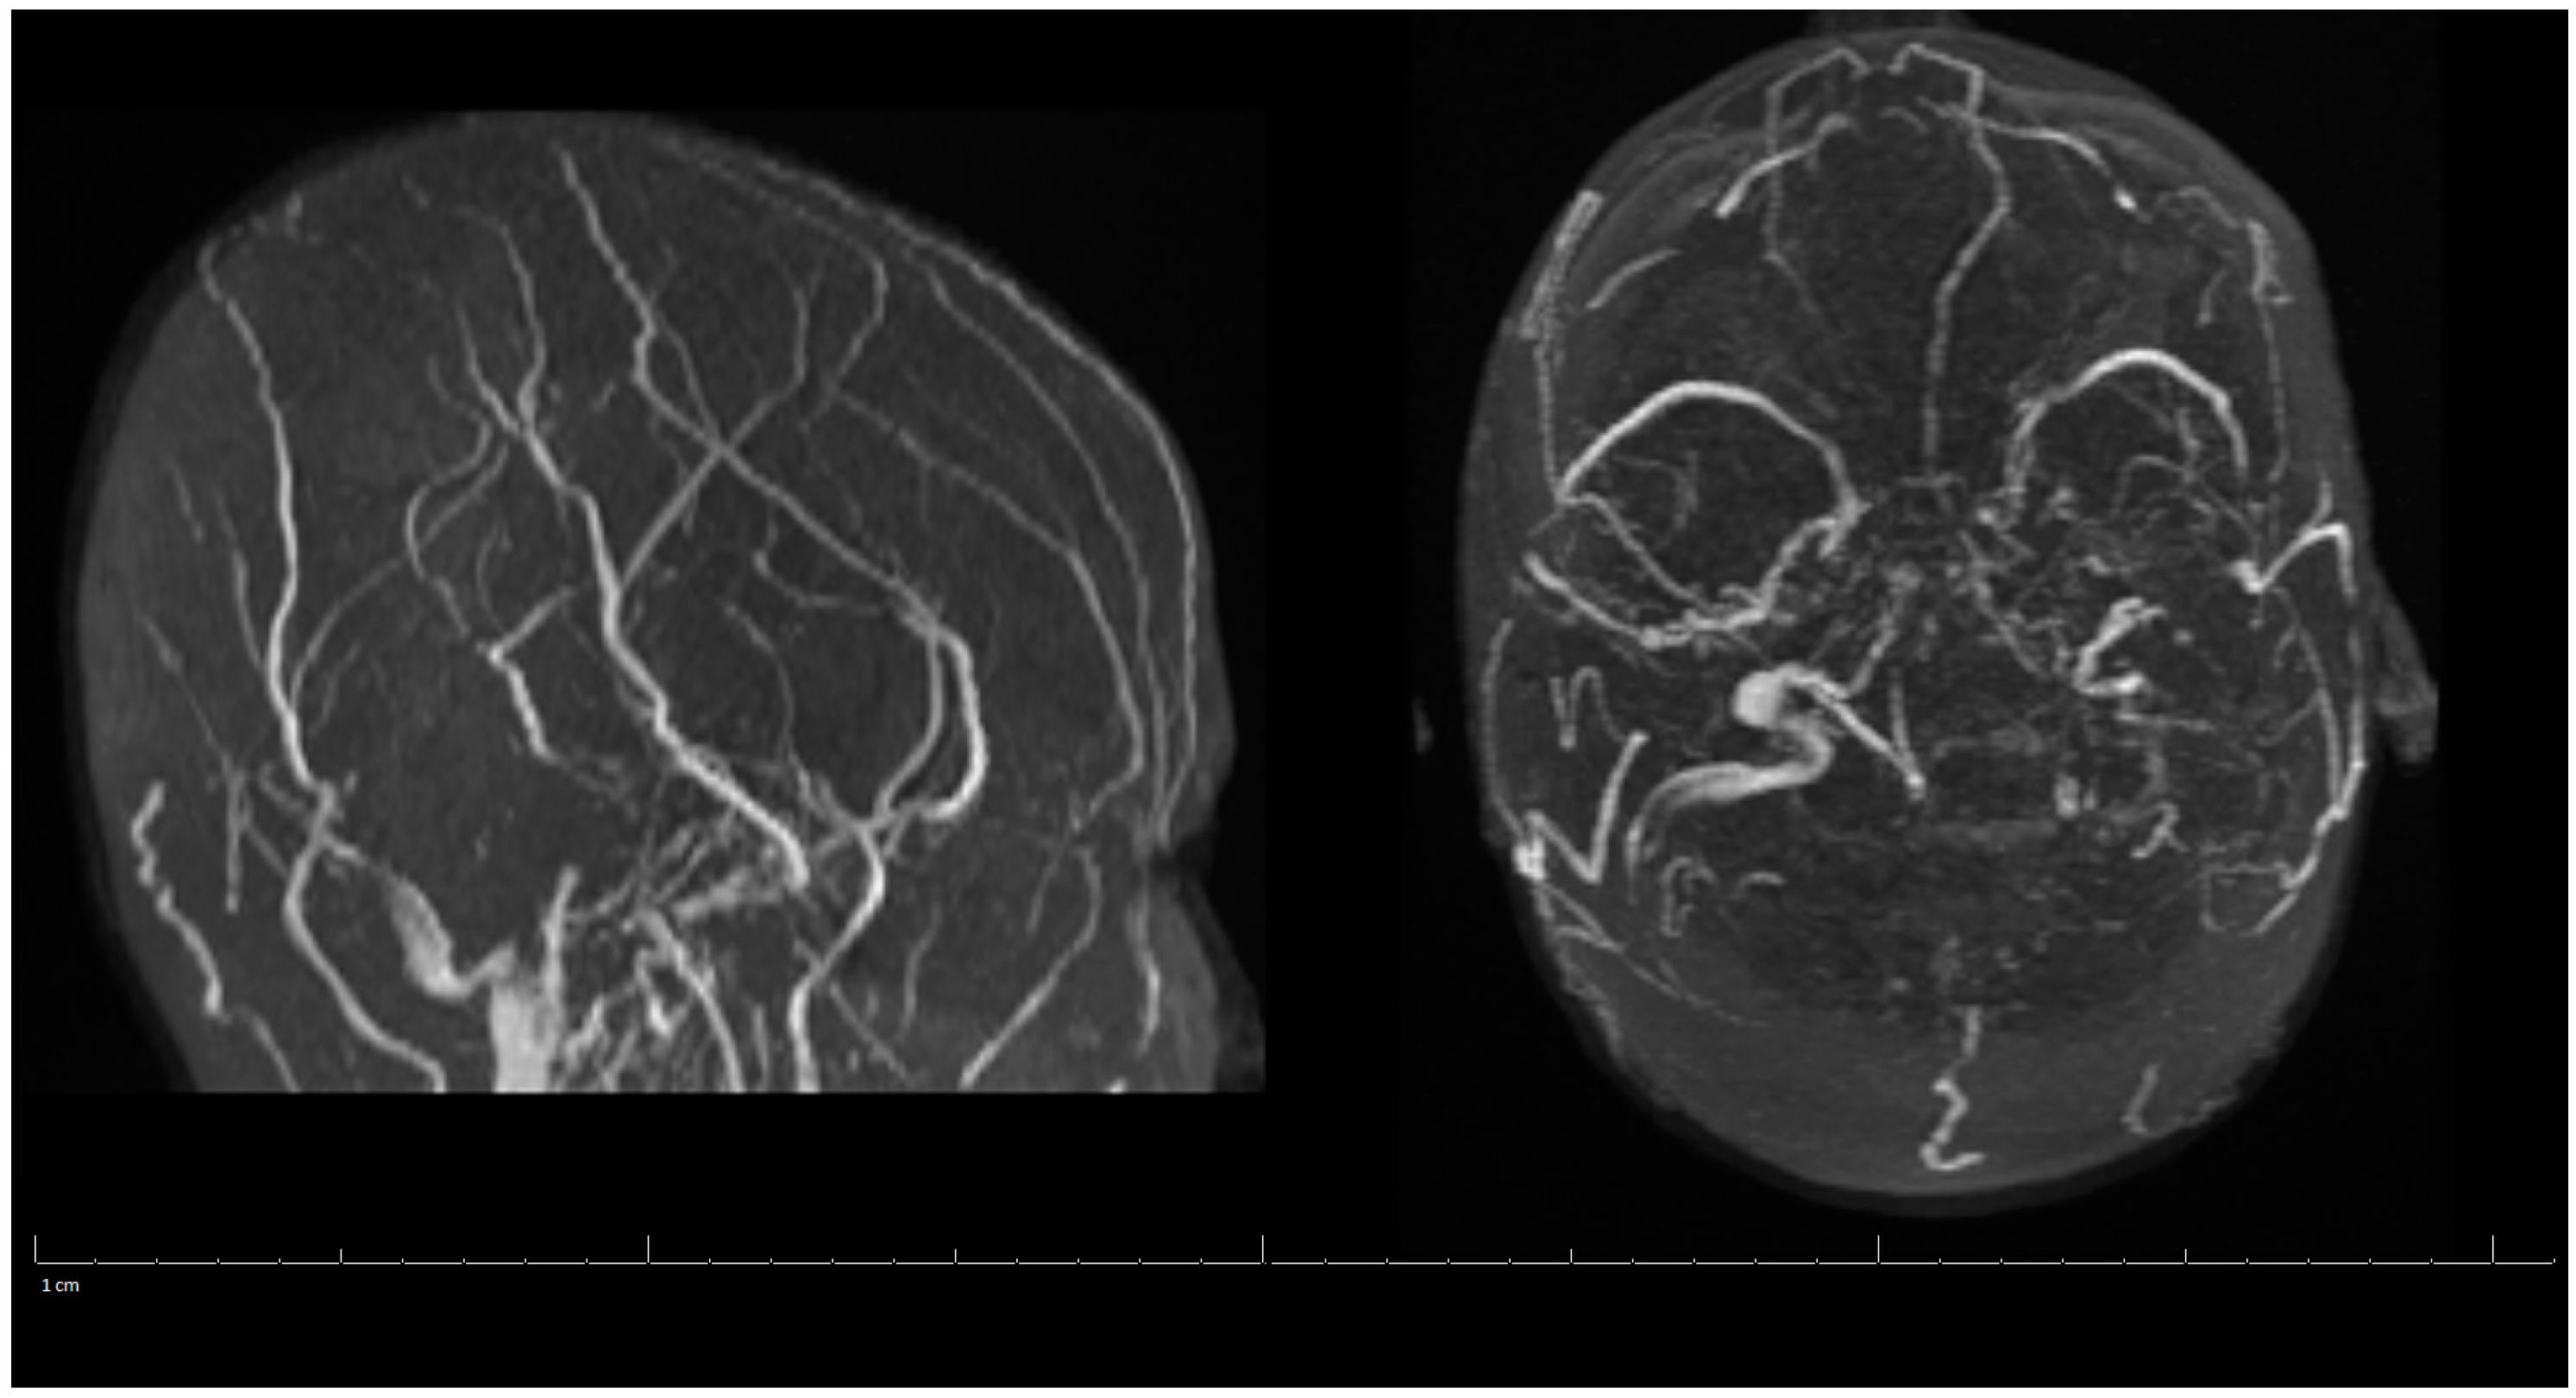

Additional labs showed Complete Blood Count (CBC) within acceptable limits, Basic Metabolic Panel (BMP) significant with glucose of 142 mg/dL, normal cardiac troponin level, and a negative urine drug screen. Urinalysis showed a small amount of blood but no evidence of infection. Genetic hypercoagulable labs, including antinuclear antibody, antineutrophil cytoplasmic antibodies, anti-cardiolipin, anti-Beta-2-glycoprotein, Factor V Leiden, and a lupus anticoagulant assay, were also unremarkable. Several hypercoagulable tests including antithrombin, protein C, and protein S were deferred, as results would have been confounded by the acute thrombotic event. Of note, the patient had abnormal findings on the lipid panel consisting of high cholesterol, triglyceride, and VLDL, and a low HDL level. Ultrasound Venous Doppler of the bilateral lower extremities showed no deep vein thrombosis. MRI brain/MRV (Magnetic Resonance Imaging (MRI) is a technique that uses magnetic fields and computer-generated radio waves to create images of organs and tissues in your body. Magnetic Resonance Venography (MRV) uses magnetic resonance technology and intravenous contrast dye to visualize the veins. Diffusion-Weighted Imaging (DWI) is a form of MRI that uses the diffusion of water molecules to generate images) with and without contrast confirmed acute venous infarct in the left subcortical frontal and parietal lobes as well as the left splenium of the corpus callosum. Thrombosis of the superior sagittal sinus, cortical veins, straight sinus, left internal cerebral vein, vein of Galen and the bilateral transverse sinuses, as well as the left sigmoid sinus, were also confirmed. A small hemorrhagic focus in the left occipital lobe was noted and was likely venous hemorrhages (Figure 1 and Figure 2). The final diagnosis was diffuse cerebral venous sinus thrombosis likely related to OCP use with possible contribution by recent COVID vaccination.

Figure 2.

MRV of the Head during Hospital Admission.